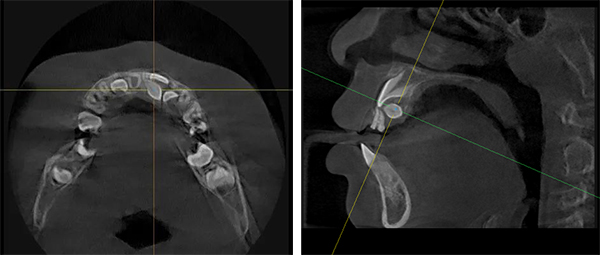

拍片子檢查是“火眼金睛”

對(duì)于藏在骨頭里的“隱身”多生牙,醫(yī)生會(huì)用“照妖鏡”——X光牙片、全景片(曲面斷層片),特別是口腔專用CT(CBCT)。

沒(méi)長(zhǎng)出來(lái)的埋伏多生牙

未標(biāo)題-3.jpg

有時(shí)會(huì)在骨頭里“作妖”,形成囊腫(像個(gè)小水泡),囊腫會(huì)慢慢“吃掉”骨頭(頜骨吸收)。